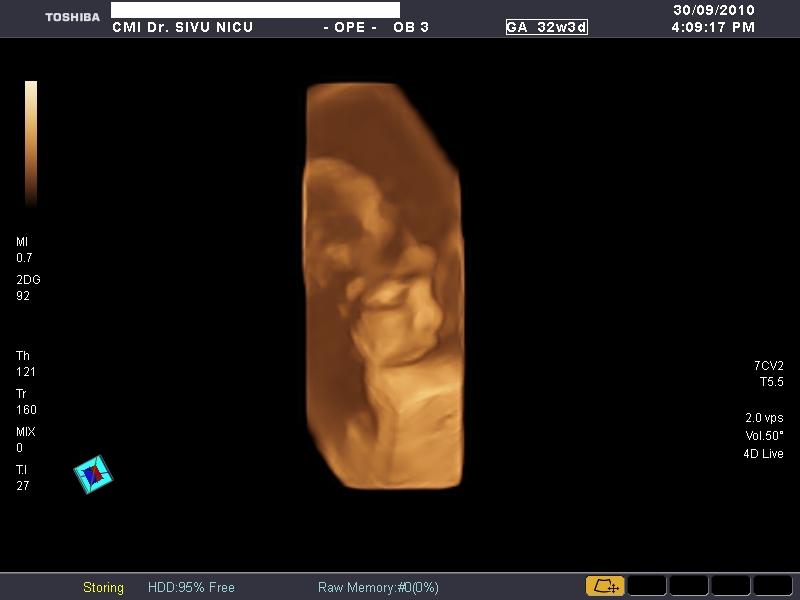

De sarcina (morfologie,biometrie,3D si 4D)

Poze realizate pe ecograful

Toshiba Applio XG